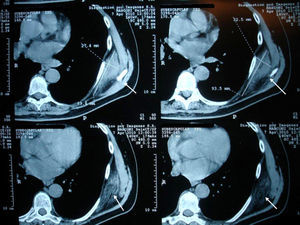

Clinical CasesCase 1A 73-year-old patient with a history of osteoarthritis in their hands presented with pain in the left scapular region of 3 months duration, which was exacerbated by physical activity, referring the pain to the scapular area of the shoulder after movement. Physical examination found a hard consistency, elastic, painless mass approximately 7cm in diameter in the left subscapular region. Ultrasonography of the affected region reported a solid mass of the chest wall, which was below the serratus anterior (Fig. 1). CT scan showed a unencapsulated occupying mass with density similar to muscle, mixed with adipose tissue bands in the left infrascapular region of 8.8 by 2.4cm (Fig. 2). Hematological and biochemical analyzes were normal. The orthopedics department suggested excision of the lesion, but the patient refused surgery. A control CT scan 2 years later showed no changes.

Imaging studies are useful for diagnosis, with ultrasound showing an alternating pattern of fasciculated type or laminar, hypo- and hyperechoic lines parallel to the chest wall and the Doppler signal is usually negative, demonstrating the absence of intrinsic vascularity. These data are usually sufficient to make a diagnosis.2,7 Ultrasound images of our patients were indicative of the lesion, although no Doppler study was performed. CT shows the alternation of adipose tissue and fibrous tissue with muscle density, not enhanced by contrast.8 MRI reported an alternating pattern of adipose and fibrous tissue and, in T1 and T2 sequences, fibrous tissue shows signs of low intensity similar to muscle. Adipose tissue shows signs of high signal intensity on T1 and intermediate T2. STIR sequences of the lesion observed areas of high and low intensity, enhanced with the use of gadolinium.9 Biopsy is reserved for suspicious cases that do not exhibit a characteristic pattern. The macroscopic appearance of the tumor is hard, elastic, yellowish-white tissue, about 5–10cm. The size of tumors in our series ranged from 2 to 9cm, coincident with what is described in the literature.2 Histopathological studies show the interposition of collagen fibers with mature adipose tissue without an inflammatory infiltrate.8 One of the patients underwent a surgical excision, but clinical and imaging studies allowed a definitive diagnosis in the others.